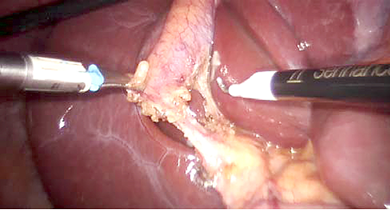

07-b_e.jpg

Figure 2. Robotic dissection in process

The patient was then placed in reverse Trendelenburg position with the right side up. The Senhance TransEnterix surgical robot was then brought into position and docked. When performing cholecystectomy with the Senhance, TransEnterix robotic system, 3 independently usable robotic arms are used (Figure 1). To prepare, we regularly use a monopolar hook (right hand/right robotic arm) and a bipolar grasper (left hand/left robotic arm) (Figure 2). The third arm is used as a camera holder. An integrated 3D camera with 16-fold magnification offers a very high-quality visible field and precise assessment of thinnest tissue structures. With ‘Eye-Sensing Control’, the camera can be maneuvered precisely by the eye movements of the surgeon after the initial calibration from the console (Figure 3). The dissection was performed according to the standard laparoscopic technique. After clear identification of the cystic duct and cystic artery, the cystic duct was ligated manually with clips. The cystic artery was coagulated or clipped just around the gallbladder. The gallbladder was dissected from the bed. Once fully dissected, the gallbladder was removed through the umbilical 18 mm port. The robot was then withdrawn, and the 18 mm port site was closed with absorbable sutures. Finally, the skin incisions at the port sites were sutured.